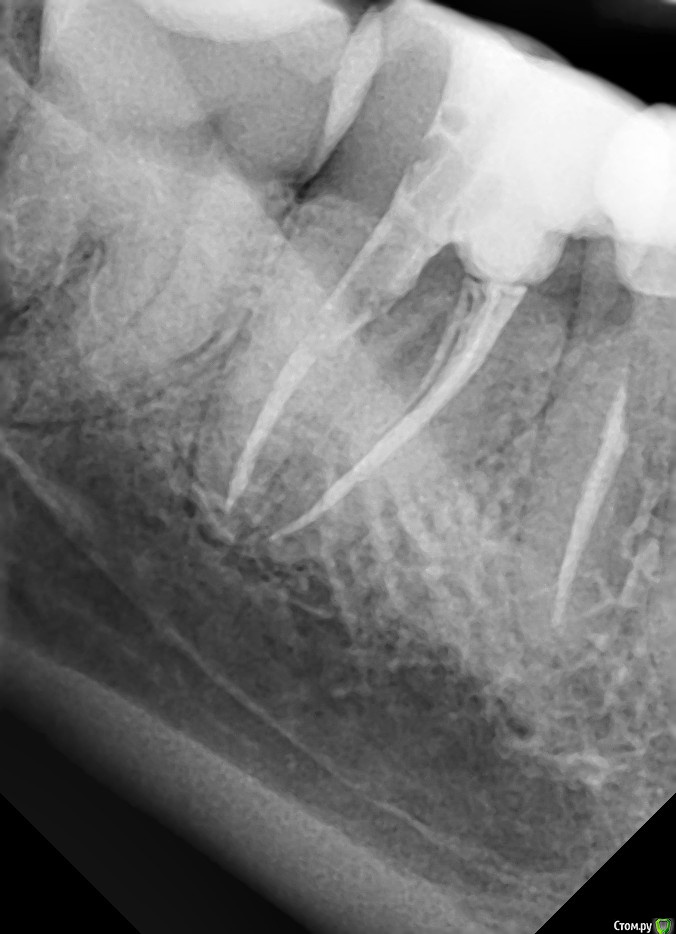

Возможно ли сохранить зуб 4.7? Прикрепляю 2 снимка: 1 - через месяц после эндодонтического лечения, 2 - через 5 месяцев после эндодонтического лечения.